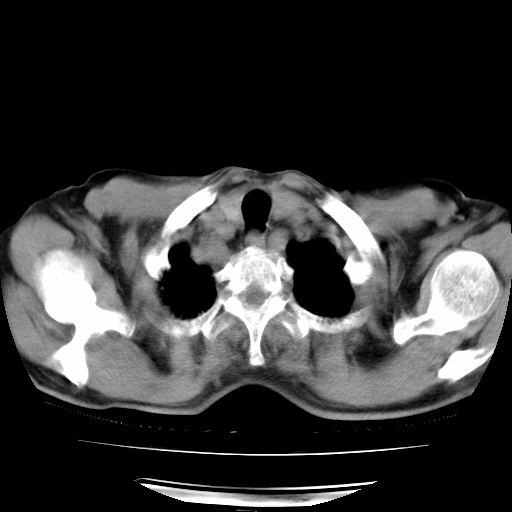

男,71岁,咳嗽,气喘10年,再发并咯血.胸片见气胸

考虑  左肺中心型肺癌伴阻塞性肺炎,肺不张,纵膈淋巴结肿大。慢支炎,肺气肿,左侧气胸肺压缩5%

左侧中央型肺癌伴纵膈淋巴结转移。

左肺中心型肺癌伴阻塞性肺炎,肺不张,纵膈淋巴结肿大

1)考虑左肺中心型肺癌伴阻塞性肺炎、左肺下叶肺不张、左侧肺气肿,纵膈淋巴结转移。2)左侧气胸(肺组织压缩约5%)。

左肺中心型肺癌伴阻塞性肺不张、肺气肿 。

1)考虑左肺中心型肺癌伴阻塞性肺炎、左肺下叶肺不张、左侧肺气肿,纵膈淋巴结转移。2)左侧气胸。